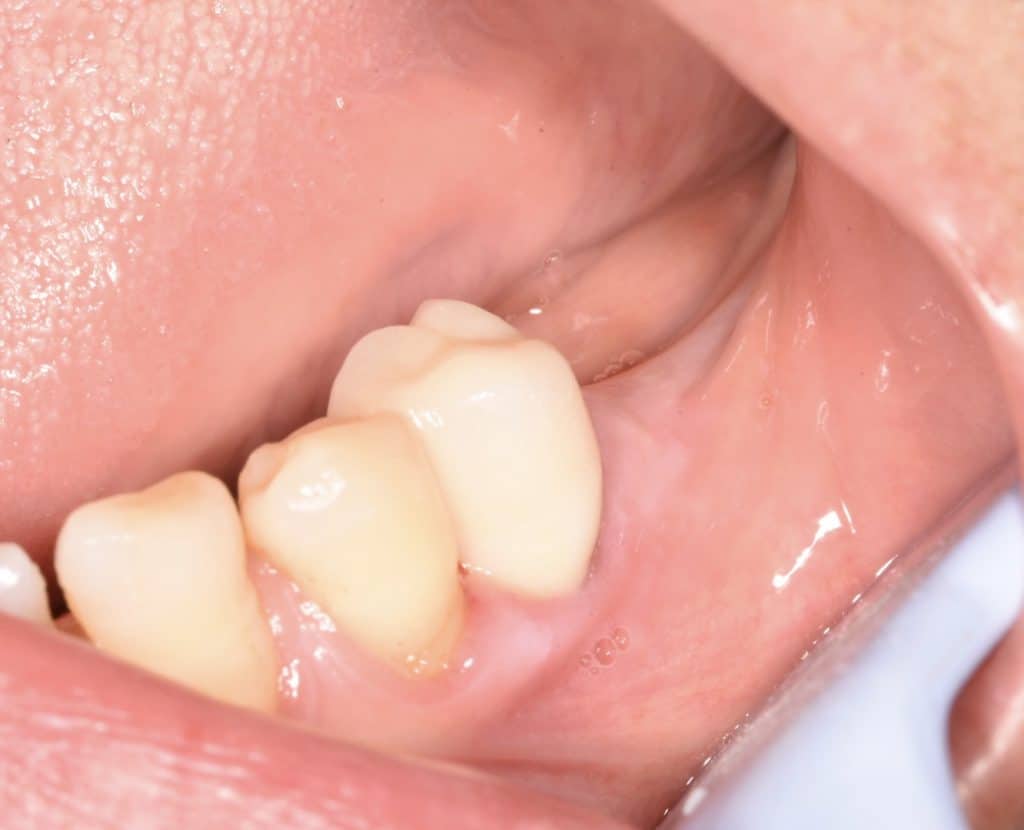

⛔️ isolation with rubber dam.

⛔️ remove all caries from tooth no. 34

⛔️ RCT

⛔️DME

⛔️use fiber post to build up the core.